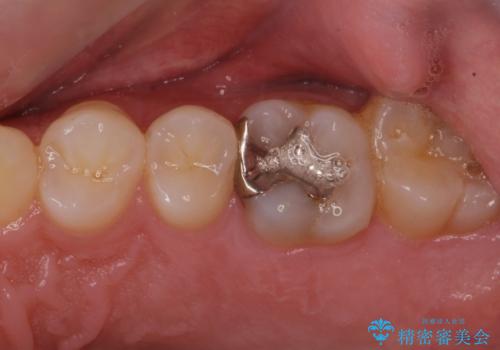

古い樹脂を除去してe-maxインレー

- 樹脂の材料での治療をセラミックに変えたいとの事で来院。

拡大鏡下で古い樹脂を除去し、虫歯がない事を確認してe-maxインレーで治療を行いました。

適合の良い詰め物が入りました。

セラミックは虫歯の再発のリスクが少ないです。